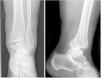

Study variablesThe initial X-rays of all the patients were reviewed, determining the type of fracture according to the Lauge-Hansen classification, and the size of the posterior malleolus was measured in millimetres. The patients were divided into three categories according to the percentage of involvement of the joint surface of the tibia: involvement <10% (group A), between 10% and 25% (group B) and >25% (group C) (Fig. 1). Joint reduction after osteosynthesis was checked in all the patients, measuring the medial clear space and the tibiofibular overlap, assuming an adequate reduction when these were less than 5mm and greater than 10mm respectively.14

After a mean follow-up period of 33 months (12–73 months) after the fracture, all the patients were reassessed in the trauma clinic, where scores of the VAS scales at rest and during exercise were taken (from 0 no pain, to 10 the worst pain imaginable) of the American Orthopaedic Foot and Ankle Society (AOFAS) for the ankle and hindfoot (0–100) and of SF-36 as a general health questionnaire. Weight-bearing X-rays were also taken (AP and lateral) to determine the degree of tibioastragaline osteoarthritis; these were all assessed by the same surgeon using the osteoarthritis classifications of Takakura15 and Van Dijk16,17 (Fig. 2).